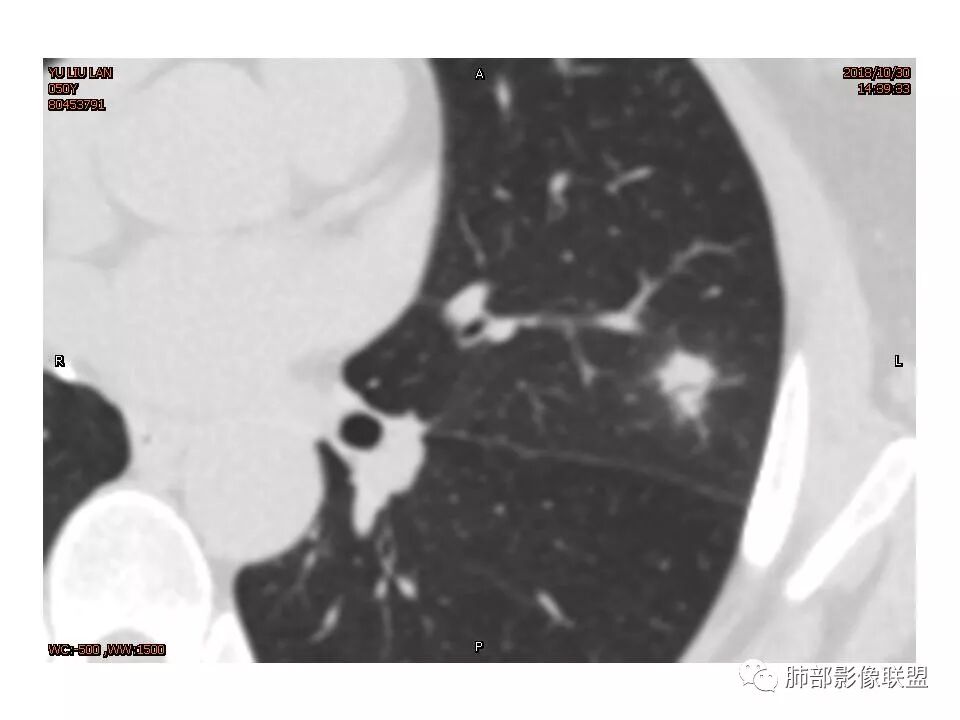

左肺上叶结节,部分边缘膨隆,边缘毛刺,斜裂牵拉,增强中度强化,血管穿行,血管略增粗。考虑肺癌,腺癌可能性大,鉴别肉芽肿性炎

左肺上叶结节影,边缘清晰(周围似见磨玻璃影,需薄层观察),分叶,粗毛刺,月牙铲,血管穿行,胸膜脐凹征,增强不均匀强化,考虑腺癌,病灶部分边缘平直,磨玻璃缘模糊,先抗炎治疗后复查

左肺上叶结节影,病灶周围呈磨玻璃样改变边缘见毛刺、分叶及胸膜牵拉,增强扫描病灶明显强化,病灶未跨叶间裂,考虑炎性病变,待除外小腺癌。

炎性征象多,平直,长毛刺,尖角征,周围晕模糊,炎性病变放前,腺癌待删,抗炎后复查

结节样病灶,u型征,病灶内可见细支气管管,增强可见血管进入,略增粗,病灶周围有晕,有软毛刺,局部叶间胸膜有牵拉,考虑良性炎性病灶,抗炎后复查。

左肺上叶结节样高密度,边缘稍模糊、平直,见长毛刺,周围血管增粗,患者体检发现,考虑隐球菌,鉴别腺癌(老年女性,似见有分叶),

左上肺结节 周围磨玻璃边缘模糊 结节周围有短及长毛刺 虽有收缩力 但病变边缘收缩较多 长毛刺对邻近外侧胸膜没什么收缩 增强有延迟强化 进入血管稍增粗 首先考虑炎性 感觉炎症吸收过程中也可以这样 腺癌待排

女性,50岁。U型凹陷、平直征

南边:支持炎性

1.胸膜下略不规则实性密度结节影,孤立,缺乏典型深分叶,可见淡薄边界模糊磨玻璃晕,可见相对细长软毛刺。

2.如南边老师分析,病灶缺乏边缘膨隆优势,甚至部分平直内收。

3.病灶收缩力不强,整体强化程度不显著。

4.综上,病灶更符合炎性,如隐球菌感染等,而不大符合肺腺癌。具体到机化性肺炎略有些出乎预料。